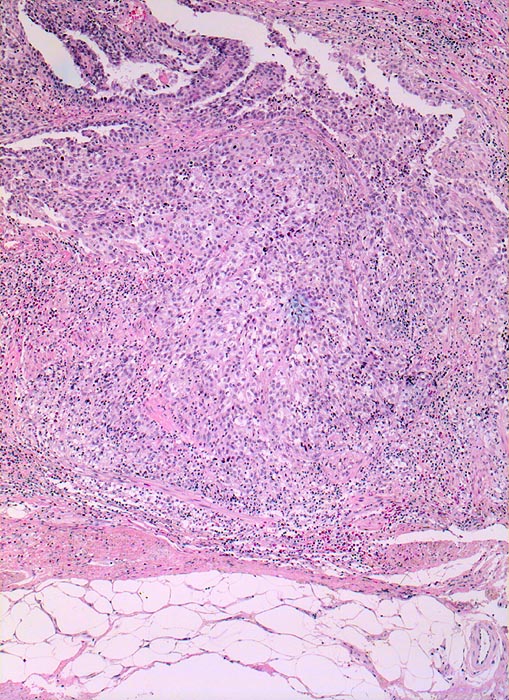

Urothelkarzinom

maligner Tumor

Harnblase

Ein solider Tumor infiltriert das perivesikale Fettgewebe.

Makrohämaturie. In der Harnblasenspülflüssigkeit werden Urothelien mit schweren Kernatypien vereinbar mit Urothelkarzinom nachgewiesen. Zystoskopisch kommt in der Hinterwand ein ulzerierter Tumor zur Darstellung. Die bioptische Abklärung ergibt Anteile eines wenig differenzierten Urothelkarzinoms mit ausgedehnten Nekrosen.

Die Infiltration des perivesikalen Fettgewebes entspricht einem Stadium pT3.

Histologie

50